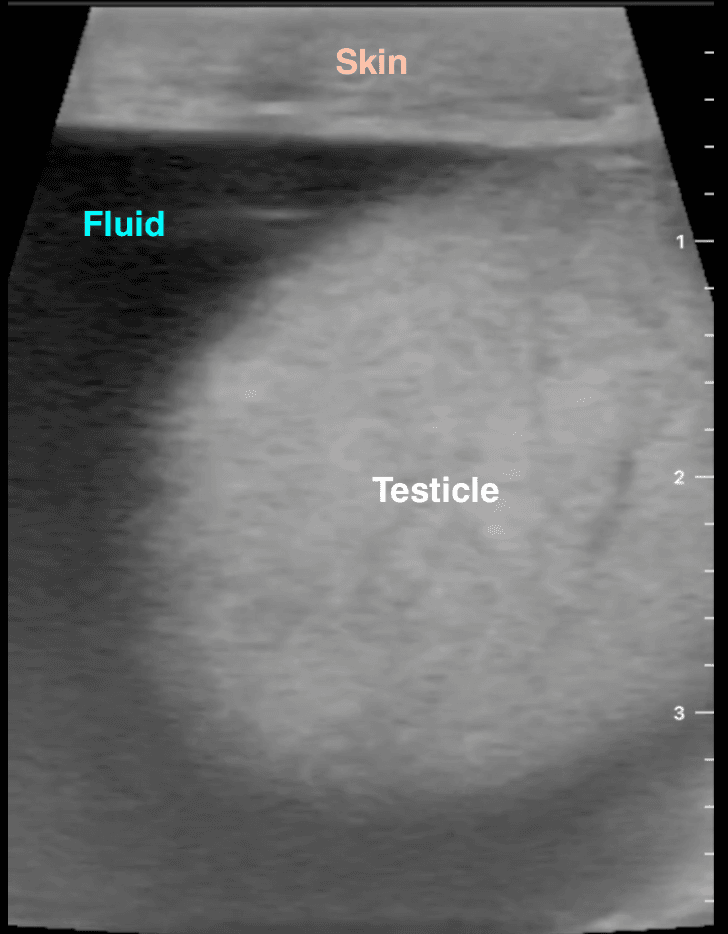

A spermatocele or spermatic cyst is an abnormal sac in the upper part of the epididymis (the epididymis is a coiled tube in the testicle that collects and transports sperm). In most cases, a spermatocele is a smooth, soft mass that contains clear or milky fluid, and sometimes, sperm. The exact reason why spermatoceles develop is unknown but it is believed to be due to a blockage in one or more of the multiple tubes within the epididymis. Spermatoceles are a relatively common problem and are often discovered by chance. Incidental spermatoceles are found in 30% of patients undergoing ultrasound of the scrotum for other complaints.

Spermatoceles are non-cancerous and they do not typically affect fertility. Most spermatoceles are painless. However, a spermatocele can grow large enough to cause discomfort, pain, and a sensation of heaviness or fullness. Spermatoceles are diagnosed by ultrasound which can be done in the office.

Our specialist performs the aspiration first using ultrasound-guidance. Ultrasound is used throughout the procedure to make sure the procedure is performed adequately and safely. The ultrasound shows precisely the location of the tube so that the testicle and adjacent structures do not get punctured, essentially eliminating any risks. Make sure that your specialist performing this procedure is trained in ultrasound-guided procedures. Our specialist performs more sclerotherapy treatments than any other specialist.